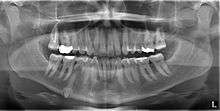

Classifications enable the oral surgeon to determine the difficulty in removal of the impacted tooth.[3] The primary factor determining the difficulty is accessibility, which is determined by adjacent teeth or other structures that impair access or delivery pathway. The majority of classification schemes are based on analysis on a radiograph. The most frequently considered factors are discussed below.

Angulation of tooth

Most commonly used classification system with respect to treatment planning. Depending on the angulation the tooth might be classified as:

Relationship of tooth to anterior border of ramus

This type of classification is based on the amount of impacted tooth that is covered with the mandibular ramus. It is known as the Pell and Gregory classification, classes 1, 2, and 3.[4]

Relationship of tooth to occlusal plane

The depth of the impacted tooth compared with the adjacent second molar gives the basis for this type of classification. This was also given by Pell and Gregory and is called as Pell and Gregory A, B and C classification.